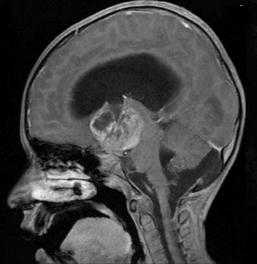

МРТ головы в сагиттальной проекции, Т1-взвешенное изображение после усиления гадолиний-содержащим контрастом: видно накапливающее контраст супраселлярное новообразование с сопутствующей гидроцефалией. Снимок девочки 7 лет с клиническими проявлениями синдрома Рассела, дебютировавшими с годовалого возраста (источник: Crawford J.R., Shayan K., Levy M.L. Delayed presentation of diencephalic syndrome associated with leptomeningeal dissemination in a child // BMJ Case Rep Published online 01/02/2013)